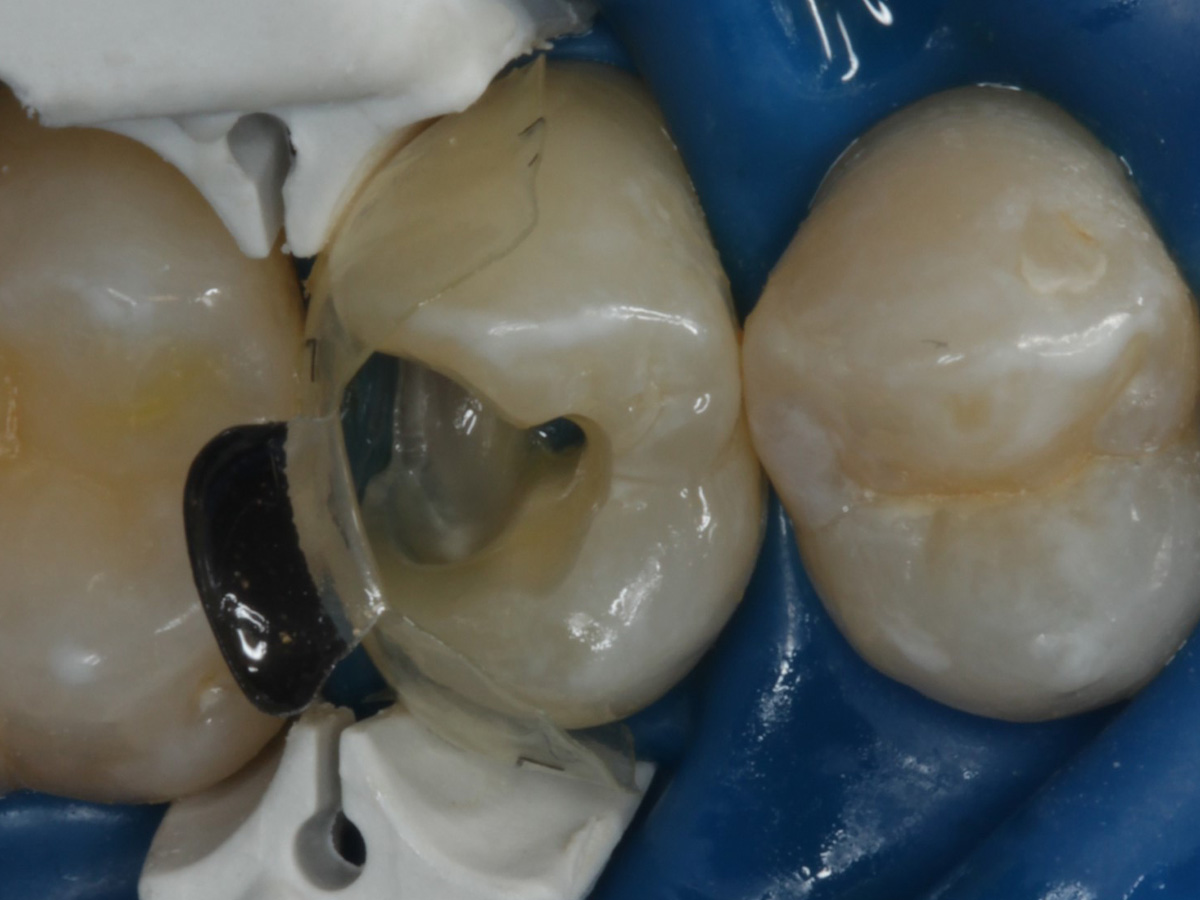

Abbildung 9

Nach Applikation der Matrize: Evolve Schwarz Prämolar- 7 mm; Schmelzätzung

Abbildung 10

Nach Spray und Trocknung der Kavität: perfekte Adaptation der Matrize insbesondere tief subgingival